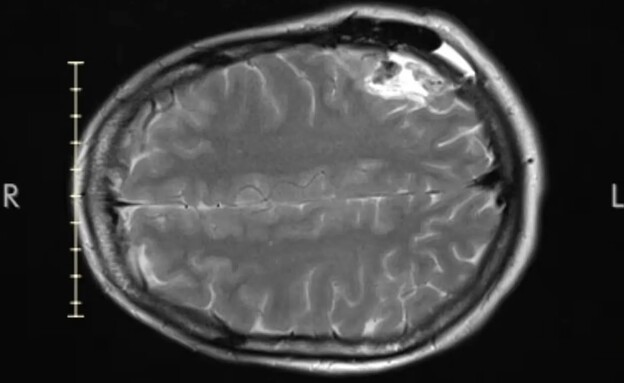

לורן נלקחה לבית החולים, שם עשו לה CT ראש. בתוצאות הבדיקה הרופאים הבחינו במה שנראה כמו צל במוח שלה - ומשם הדרך הייתה קצרה לאבחנה הקשה: סרטן המוח. ללורן נאמר כי המחלה סופנית, וכי נשארו לה בין 10 ל-12 שנים לחיות.

חודש לאחר מכן לורן חזרה לבית החולים, ושם קיבלה חדשות גרועות אפילו יותר. הרופאים התעמקו בתוצאות הבדיקה שלה, ושינו את אבחנתם - לפי החשד החדש שלהם מה שיש לה הוא גליובלסטומה, גידול סרטני אלים ומתקדם במוח. המשמעות היא שתוחלת החיים המוערכת שלה תהיה כנראה קצרה יותר ממה שנאמר לה קודם. ״לא ציפינו לזה״, שיתפה לורן. ״ואז זה הכה בי. זה הרגע שבו את מבינה, ׳אלוהים אדירים, יש מצב שאני מסתכלת על [תוחלת חיים של] שנתיים׳״.

לורן השתמשה בביטוח הבריאות של בן זוגה כדי לעבור ניתוח להסרת הגידול במרפאה פרטית באוקטובר האחרון. הרופאים הצליחו להסיר 80% מהגידול במוחה של לורן, אבל הצרות לא הסתיימו שם. תוצאות ביופסיה הראו כי ללורן יש אוליגודנדרוגליומה בדרגה 2, סוג של גידול במוח שנמצא בשלביו הראשונים. שלה נמצא באזור במוח שאחראי על דיבור, מה שגרם לה לאובדן יכולת הדיבור ולאובדן של מרבית התפקוד הקוגניטיבי שלה.